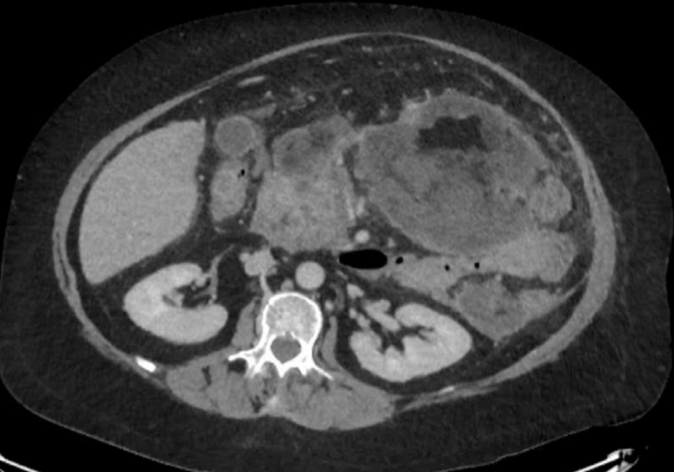

Post-ERCP acute infected necrotising pancreatitis in a patient with Cushing’s disease

Piero Alberti